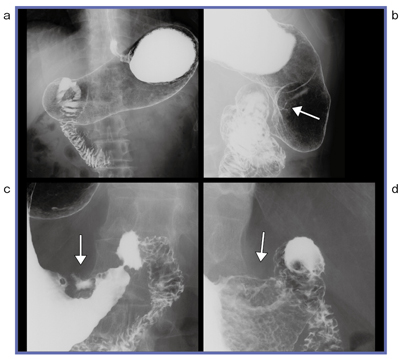

●症例1(図1)

背臥位正面位(a)ではわからず,回転中に気づいた症例である。通常見られない異常な線(b←)の部分を意識して,後半に追加撮影を行った。腹臥位圧迫して病変を描出し(c),不整なバリウム斑と周辺の厚みのある隆起などの病態,形態を撮影像として残すことで(d),医師の読影に役立つ。

図1 症例1